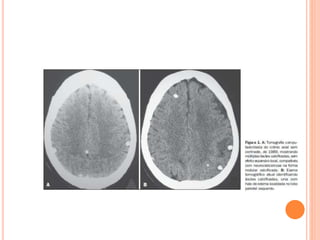

ABSCESSO CEREBRAL

 Neurocisticercose: clínica +tc+rm

DIAGNÓSTICO  Exame defezes: tentar diferenciar as tênias  Exame visual das proglótidas grávidas  Visualizar escólex  Neurocisticercose: clínica +tc+rm  Rx  Imunoblot (alta sensibilidade e especificidade)  Lcr com eosinofilia